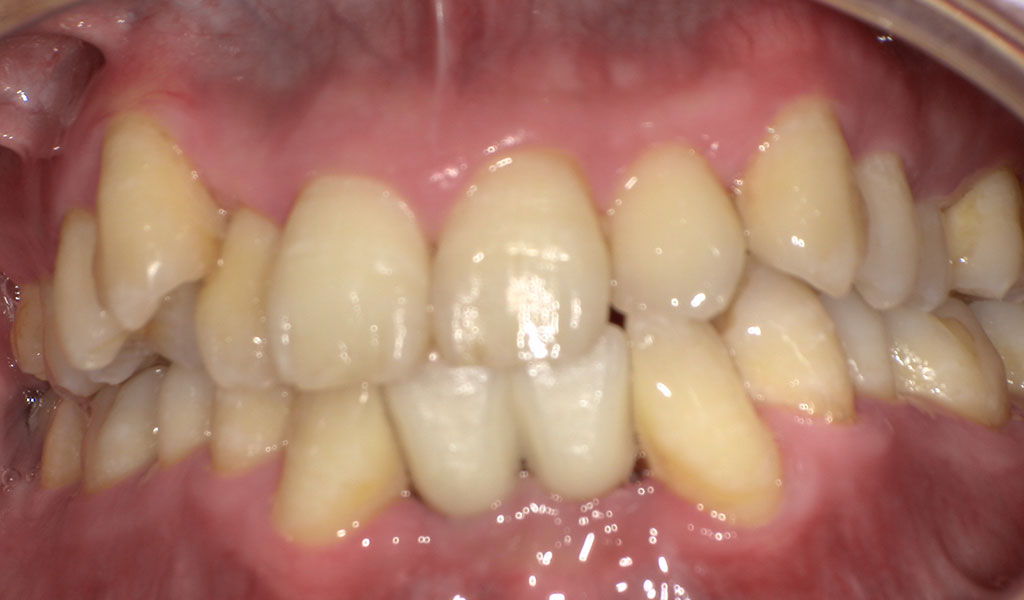

40代男性・横浜市在住。前歯下右1番欠損、 右2番、左1,2番がぐらぐらしているため、当院にて抜歯およびインプラント治療。人工歯はジルコニア人工歯。スクリューリテインにて固定しました。歯周病菌の数が多いため、歯周内科治療も実施しました。

Before1

40代男性・横浜市在住。前歯下右1番欠損、 右2番、左1,2番がぐらぐらしているため、当院にて抜歯およびインプラント治療を希望されてご来院されました。